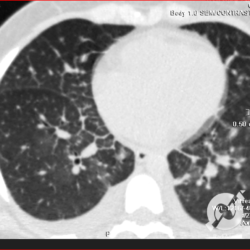

Opacidades em vidro fosco difusas com espessamento liso de septos e moderado derrame pleural bilateral.

Opacidades em vidro fosco difusas com espessamento liso de septos e pequeno derrame pleural bilateral.